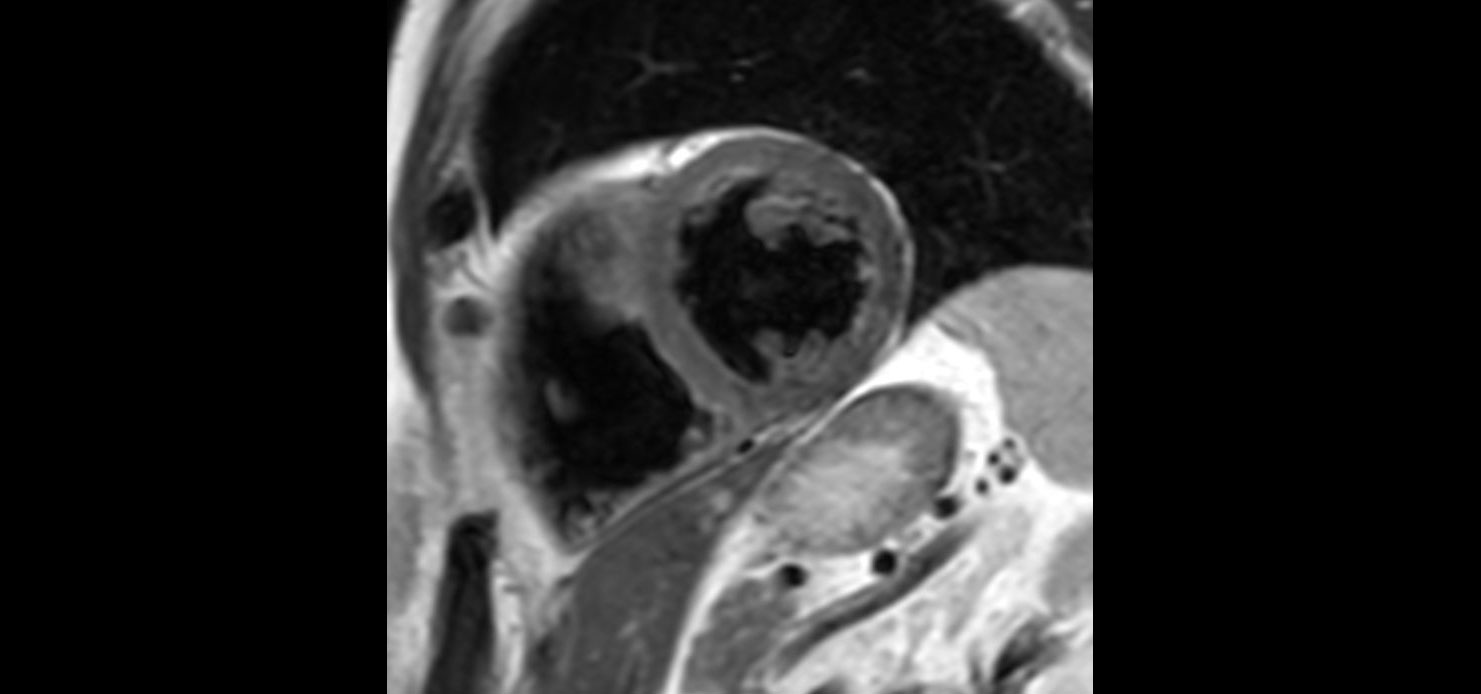

bTFE short axis Without Compressed SENSE: 8.4 sec breath hold

-

bTFE short axis With Compressed SENSE: 4.8 sec breath hold